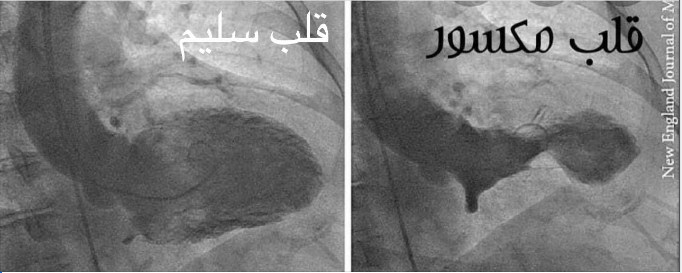

وكتب الدكتور جمال شعبان، في تدوينة له بالفيس بوك، عن ارتباط الحزن و"الزعل" بالأزمة القلبية وانكسار القلب "أيوة الزعل ممكن يعمل سكتة قلبية وموت مفاجيء كمان.. بص للصورة اللي علي اليمين دا قلب مكسور.. شوف الفرق بينه وبين الصورة اللي ع الشمال قلب سليم"

وأضاف "عاصفة الأدرينالين.. الأدرينالين بيعمل اعتصار للقلب فبيحصل انقباض في قاعدة القلب وتمدد بالوني في قمة القلب زي ما هو باين في الصورة انكسار حقيقي للقلب، رغم إن قسطرة الشرايين التاجية ممكن تطلع سليمة"